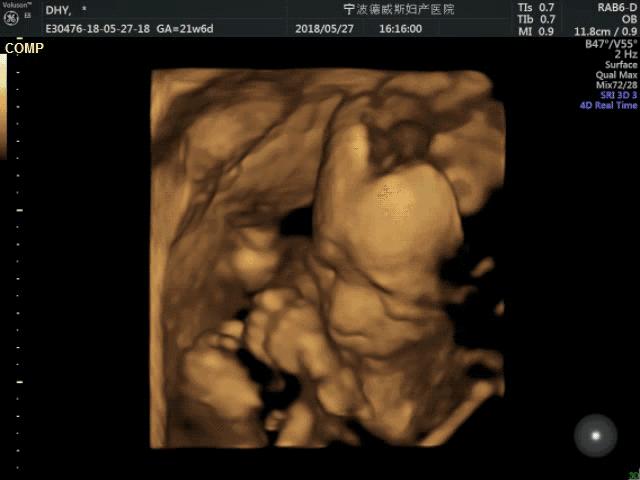

一般在20-28周就可以预约做四维了,但是不同的医院要求不同,有的必须在22-24周做四维,有的就宽泛些,在20-28周都可以。我同事有在26周做四维的,结果也不错。

还有一个原因是,这时胎儿的骨骼回声比较小,能比较清晰地看到胎儿的各个结构。

第三个原因是,这是胎儿的外形发育基本完善,接近出生时的样貌,这时结构完整的胎儿一般不会再有变化了。

我们都知道四维检查就是大排畸检查,三维检查也能做大排畸,但是四维多了一个时间维度,可以看到胎儿的动态图像,能观察到胎儿的运动神经是否正常,所以四维还是更有优势一些。